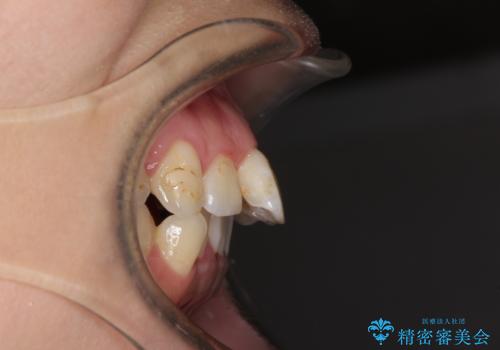

- 出っ歯と口の閉じにくさ、デコボコを気にして来院された患者様です。

口元の突出感を改善するため、上下左右第一小臼歯4本の抜歯を行い、ワイヤー装置による矯正治療を行うこととしました。